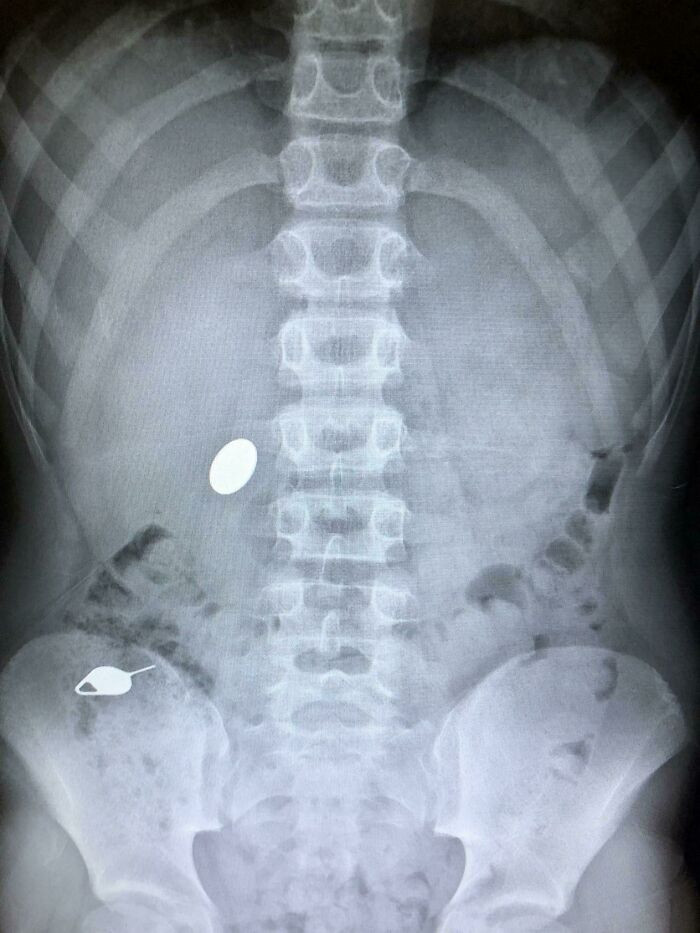

Kid swallows a nickel, and parents had to pay $4,400 to have it removed.

Kid swallows a nickel, and parents had to pay $4,400 to have it removed.Kingsdontbeg